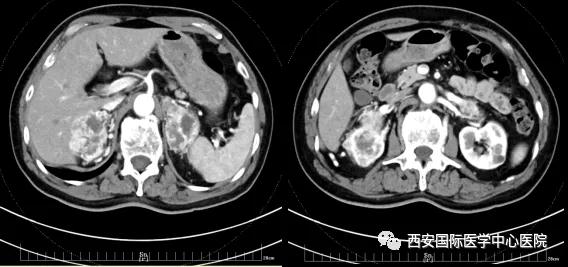

今年七十五歲的患者,來(lái)自陜西省商洛市,四月前因腰背部疼痛就診于當(dāng)?shù)蒯t(yī)院,行CT檢查發(fā)現(xiàn)“右腎、雙側(cè)腎上腺占位,前縱膈淋巴結(jié)腫大,雙肺多發(fā)結(jié)節(jié)、胸椎骨質(zhì)破壞,考慮轉(zhuǎn)移瘤”。為進(jìn)一步診斷治療,患者的兒子帶他來(lái)到西安某三甲醫(yī)院,查泌尿系CT提示“右腎占位性病變,多考慮腎癌,雙側(cè)腎上腺多發(fā)轉(zhuǎn)移灶,腹膜后多發(fā)腫大淋巴結(jié)”;行穿刺活檢提示“腎透明細(xì)胞癌”;并給予患者口服靶向藥物的治療方案。

自四月份至今,患者一直口服靶向藥物治療(阿昔替尼5mg 2次/日),期間無(wú)不良反應(yīng),目前腰背部疼痛癥狀也有所緩解,復(fù)查影像學(xué)資料提示瘤體較前縮小,腫瘤完整切除的可能性明顯提高;而且患者的兒子也是一名外科醫(yī)生,所以他更想為父親完成后續(xù)的手術(shù)治療。

患者一家慕名前來(lái)到西安國(guó)際醫(yī)學(xué)中心醫(yī)院找到楊增悅教授。楊增悅教授仔細(xì)看完患者的之前的影像學(xué)及病理資料后,診斷為:右腎透明細(xì)胞癌(T4N1M1);并安排他住院。而后,主管醫(yī)生及時(shí)為他完善了術(shù)前檢查及評(píng)估。7月15日,在麻醉手術(shù)中心柴偉主任、王彬榮副主任、李娟護(hù)士長(zhǎng)、李瑞剛護(hù)士長(zhǎng)及全體麻醉手術(shù)中心團(tuán)隊(duì)的有力保障下,成功完成了這臺(tái)“大”手術(shù)。

手術(shù)由楊增悅教授主持,舒濤主治醫(yī)師、王東主治醫(yī)師主刀,黃怡醫(yī)師、王平醫(yī)師協(xié)助完成。由于第四代達(dá)芬奇機(jī)器人更加靈活和精準(zhǔn)的特性,手術(shù)全程順利,尤其是完全精準(zhǔn)的“解鎖”了右腎動(dòng)脈和右腎靜脈的數(shù)十根交互纏繞的分支血管。術(shù)后患者麻醉恢復(fù)后生命體征平穩(wěn),順利返回泌尿外科普通病區(qū)進(jìn)一步康復(fù)。